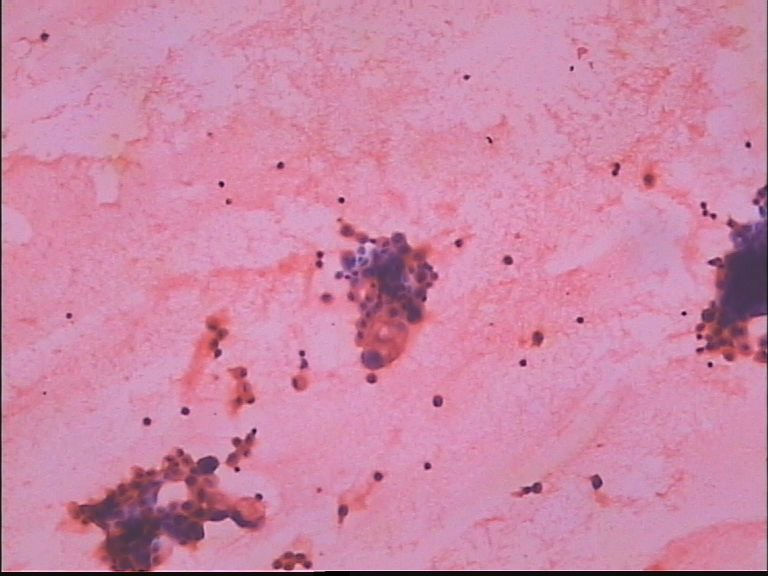

胸水 男67岁

细胞染色太深,不清楚。

见异形细胞,考虑为腺癌

从排列方式看有点像是腺癌,不过高倍镜下看那些成团的细胞胞浆还挺丰富,核也不是特别大,是淋巴细胞核的两倍左右,而且图片中的几个高倍镜显示的细胞都有点退变。认为最好还是问一下病史,看看有没有肿瘤指征,报个异型细胞,建议再送放心些。

细胞有异型,但细胞核的结构不是很清楚,癌疑,建议再检,做个细胞块更好,以便必要时做IHC.

考虑腺癌,这其中有间皮细胞。

低倍镜下那些深染的成团的都是腺样结构细胞吗?应该是腺癌。

成簇排列的细胞团有点可疑,但直接诊断恶性不够,建议再次送检或做细胞蜡块看看会有帮助吧